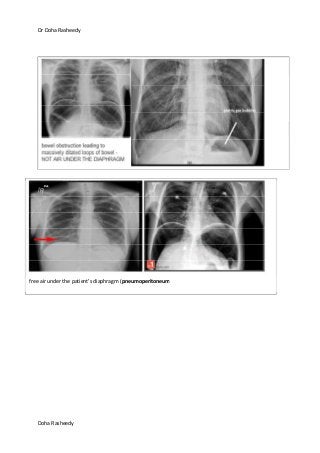

Air under Diaphragm

Plain film of the chest X-ray (A) and simple abdomen (B). After colon perforation, free air under the both

diaphragm were noted.

free air under the patient’s diaphragm (pneumoperitoneum